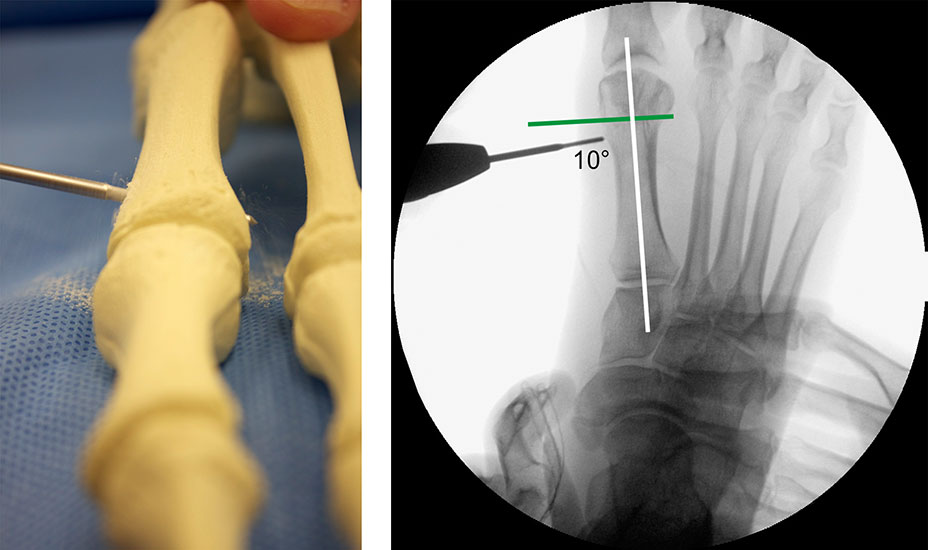

Präoperatives Röntgenbild Fuß d.p. mit eingezeichneten Winkeln. A) Intermetatarsalwinkel, B) Hallux valgus Winkel, C) Interphalangeal-Winkel.

Abbildung 2

• Operationsplanung anhand der Röntgenaufnahmen unter Beachtung wichtiger radiologischer Landmarks wie Intermetatarsalwinkel, Hallux valgus – Winkel, distaler Gelenkflächenwinkel (Distal Metatarsal Articular Angulation - DMAA), Metatarsaleindex und Sesambeinposition (Abb. 2).